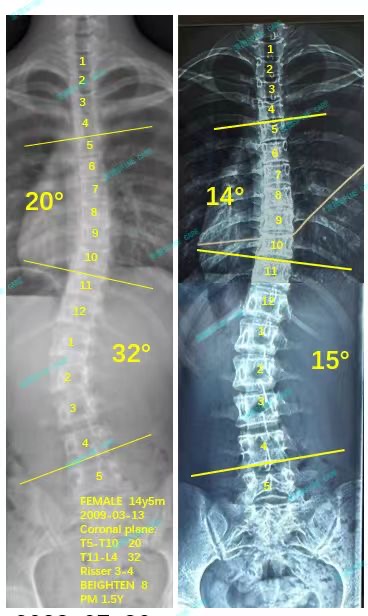

来到衷德不知不觉两年多了,我和妈妈都十分信赖杨博士和所有康复师,最近脱支后拍x片显示我的胸弯从20度降到了14度,腰弯从32度降到了15度,我很开心!

It has been more than two years since I came to Zhongde without realizing it. My mother and I trust Dr. Yang and all rehabilitation therapists very much. Recently, an x-ray without wearing brace showed that my chest bend dropped from 20 degrees to 14 degrees, and my waist bend dropped from 32 degrees to 15 degrees, I am very happy!

我现在已经上高中了,可以开始夜间佩戴支具,但是我还会继续来衷德脊柱做训练,直到我完全脱掉支具!直到我不会再加重!

I am now in high school and can start wearing braces only at night, but I will continue to come to Zhongde for spinal training until I completely remove the braces! Until I won't get worse!